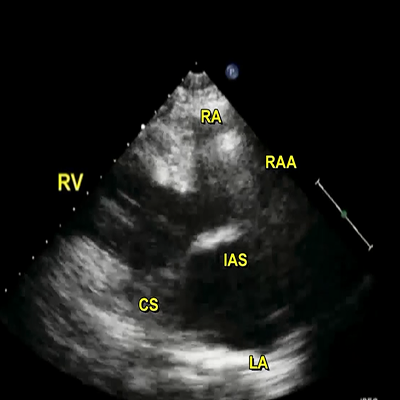

Rheumatic mitral stenosis

Rheumatic mitral stenosis